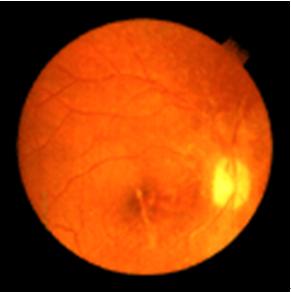

2.眼底改變

早期可見黃斑部呈顆粒狀色素脫失,中心凹光反射彌散,黃斑區呈錫箔樣。有的雙眼黃斑部出現水腫及滲出物、色素斑點,中心凹反光彌散。病情逐漸發展,兩眼黃斑部表現為環形或卵圓形邊界清楚的病變區。該區色素上皮及脈絡膜毛細血管消失。脈絡膜大血管呈白線狀,這種病變一般可以發展到50歲以上,病變區內脈絡膜的血管亦可閉塞。隨著病程發展,黃斑部漸形成類圓形境界清楚的鑿孔樣萎縮區,雙眼基本對稱,病灶呈灰綠色,有青銅樣反光,其中摻雜有棕黑色及黃白色小點,其內可見脈絡膜血管及白色鞏膜背景。所有病變都局限於黃斑區或黃斑旁區,從不累及視盤及中央區以外的區域。